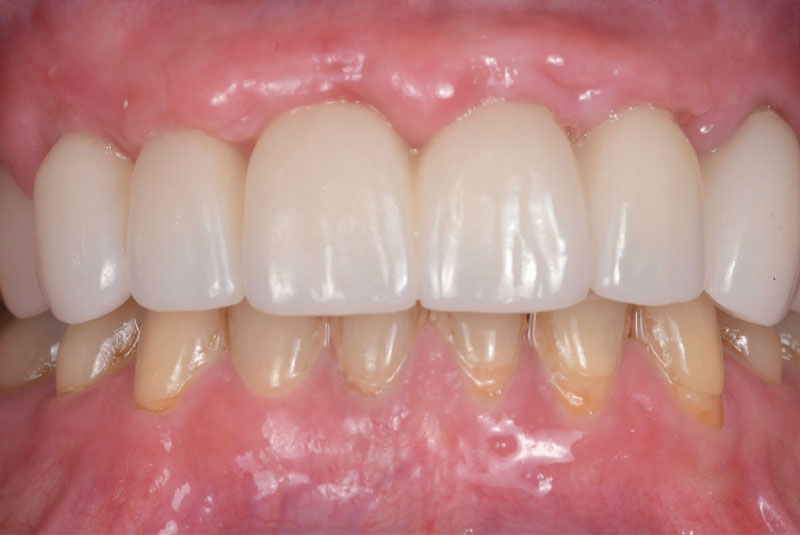

Before & After Crowns (#6,7,8,9,10,11,22,23,24,25,26,27), Overlay (#3,4,13,14,21,28,29), Implant & Implant Crowns (#5,12,19,20,30)